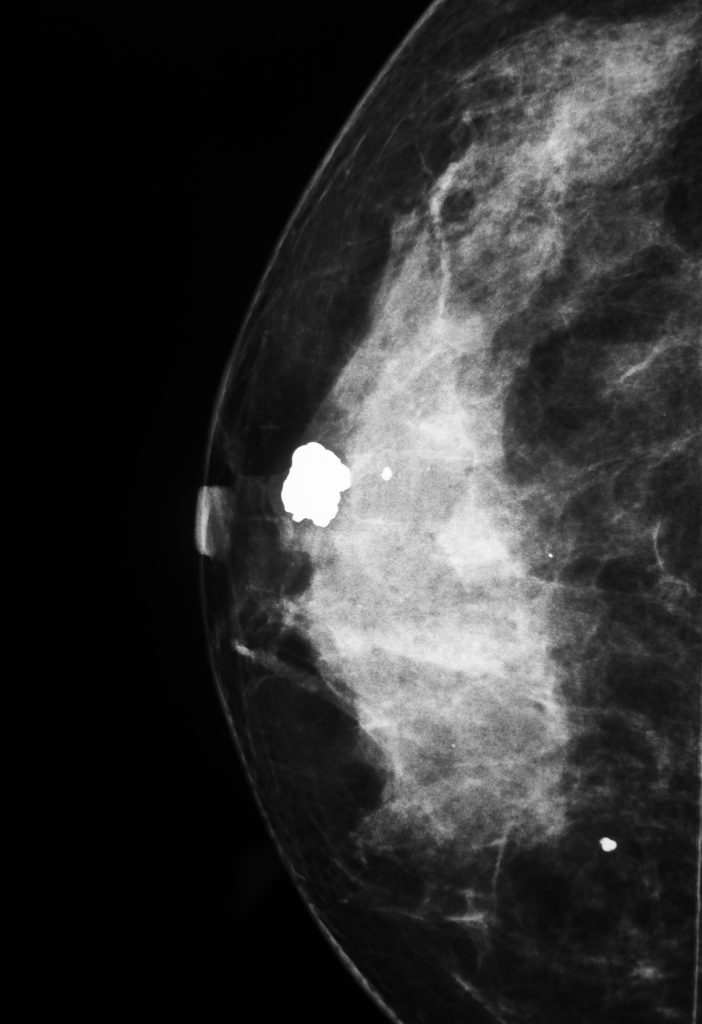

Prevenção e Detecção Precoce do Câncer de Mama: Um dos principais focos da mastologia é a prevenção e a detecção precoce do câncer de mama, uma das principais causas de morte entre as mulheres. Os mastologistas realizam exames clínicos das mamas, orientam sobre a realização da mamografia e ensinam a técnica correta do autoexame, contribuindo para o diagnóstico precoce e aumentando as chances de tratamento bem-sucedido.